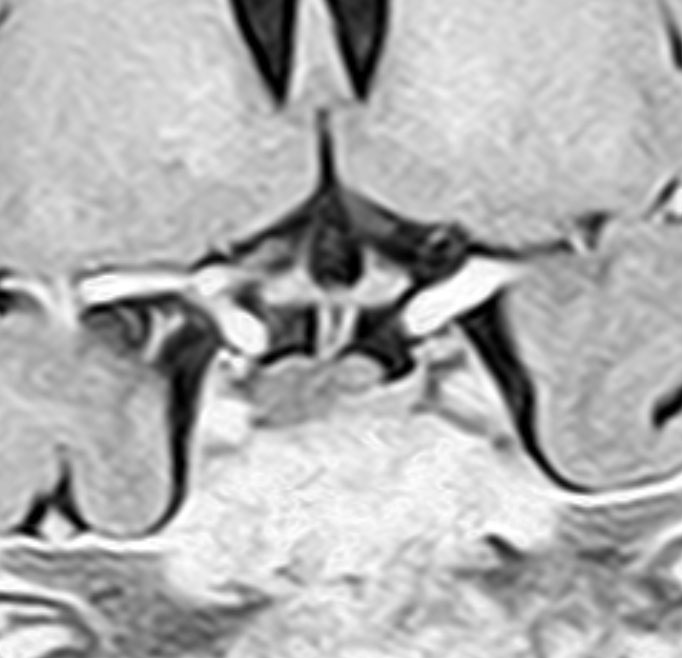

尿崩症で発症した小さな腫瘍

尿崩症で発症した9歳男児にみられたxanthogranuloma of the sellar resion。左はT1強調画像で高信号,右はT2強調画像で低信号であり,肉芽腫の特徴がみられます。のう胞部分はT2強調画像で,高信号になります(右図)。このような小さな頭蓋咽頭腫やラトケのう胞が尿崩症を呈することはまれですが,黄色肉芽腫の場合は小さくても症候性となることが多いです。神経下垂体組織が炎症性に破壊されるからと考えられます。